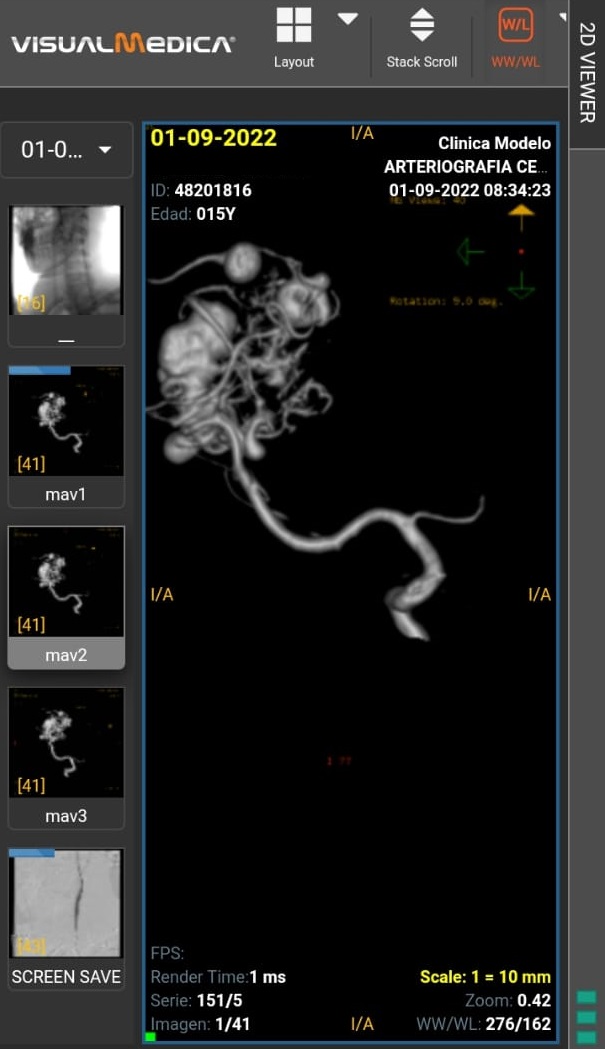

Una adolescente de 15 años de Bovril que sufre episodios de parálisis, fue diagnosticada con una malformación congénita venosa en el cerebro, por lo que enfrenta un tratamiento con un costo millonario que cursará en la Fundación Favaloro de Capital Federal.

"Ella se encuentra en tratamiento neurológico que consta de embolizaciones cerebrales y posibles cirugías y radioterapia. Dicho tratamiento no está cubierto en su totalidad por la obra social (Iosper) y debe llevarse a cabo en la clínica Favaloro. Es un tratamiento muy costoso, y a eso debemos sumarle gastos de traslado y hospedaje en Buenos Aires", explicó a La Sexta Sergio Espinoza.